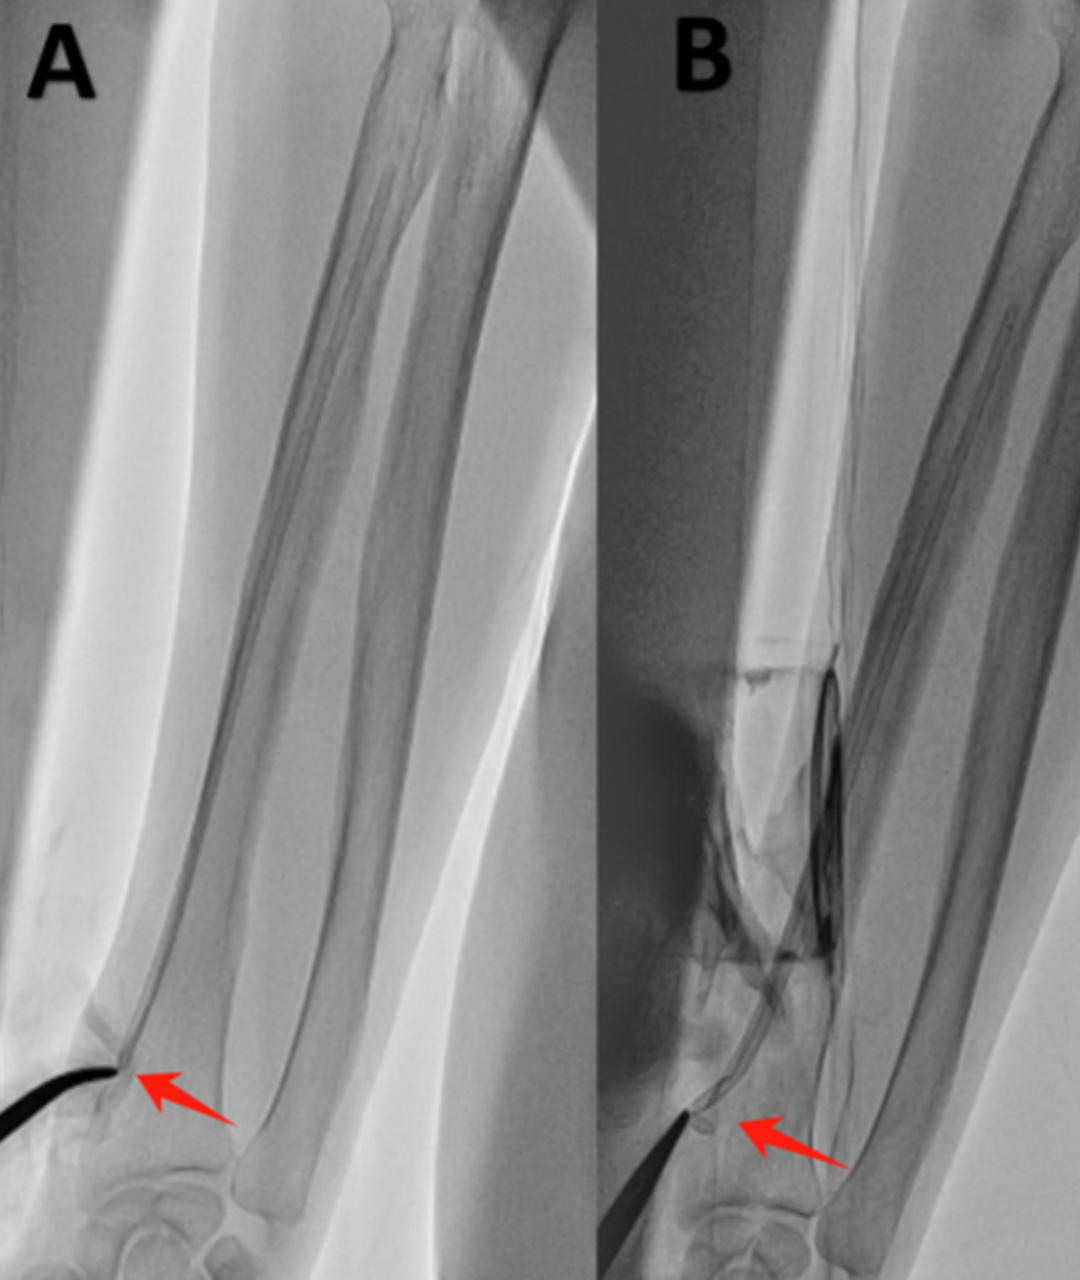

移除桡动脉鞘管时发现鞘管远心端断裂,鞘管残端完全滞留于右桡动脉内:

1. 立即压迫穿刺点止血

2. 透视观察鞘管残端(鞘管残端恰位于穿刺口下方)

3. 使用刀片扩大穿刺口,在透视引导下用止血钳深入皮下组织,尝试夹取鞘管残端

4. 幸运的是,止血钳抓住鞘管残端,小心而轻柔地取出残端

5. 移除鞘管后,立即用桡动脉止血器加压包扎。体外拼接鞘管断裂部分,反复检查以确保没有异物留在体内

(A)鞘管残端的位置 (B)止血钳夹取残端 (C)取出后的断裂鞘管